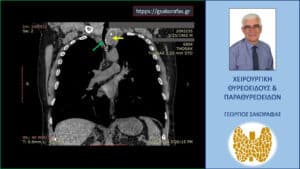

Ευμεγέθης καταδυόμενη βρογχοκήλη – απεικόνιση στην αξονική τομογραφία (σε κατά μέτωπο διατομή). Ο καταδυόμενος αριστερός λοβός του θυρεοειδούς (κίτρινο βέλος) φθάνει εγγύς στο αορτικό τόξο και απωθεί την τραχεία προς τα δεξιά (πράσινο βέλος) προκαλώντας στένωση του αυλού της.

Απεικόνιση στην αξονική τομογραφία σε κατά μέτωπο διατομή (σε άλλο επίπεδο) όπου ο καταδυόμενος αριστερός λοβός του θυρεοειδούς (κίτρινο βέλος) φαίνεται να βρίσκεται μεταξύ της έκφυσης της αριστερής κοινής καρωτίδας και της ανωνύμου αρτηρίας από το αορτικό τόξο (ΑΟ).